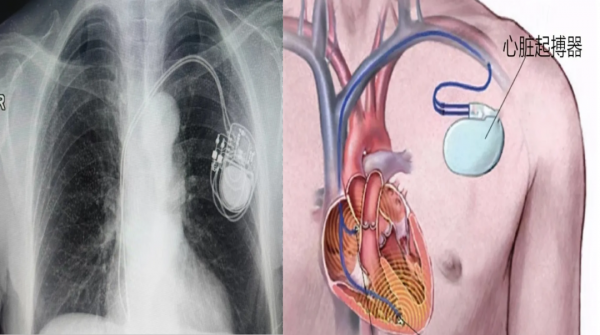

心脏起搏器植入

适用于严重心动过缓、窦房结功能不全、高度房室阻滞等。

案例:84岁女性,永久起搏器植入,总费用约5.9万元。

手术微创,局部麻醉,术后12小时可下床活动。